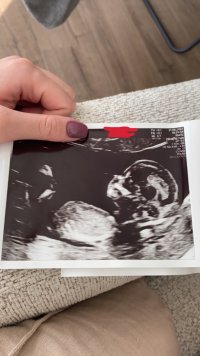

@lyse gul vil du gjette om det er jente eller gutt?Vet ikke om det er mulig å se en nub her?Jordmor ville/kunne vertfall ikke si noe - 14+0

har du flere bilder? synes ikke det er noe tydelig kjønnsorgan på disse.Vet ikke om det er mulig å se en nub her?Jordmor ville/kunne vertfall ikke si noe - 14+0